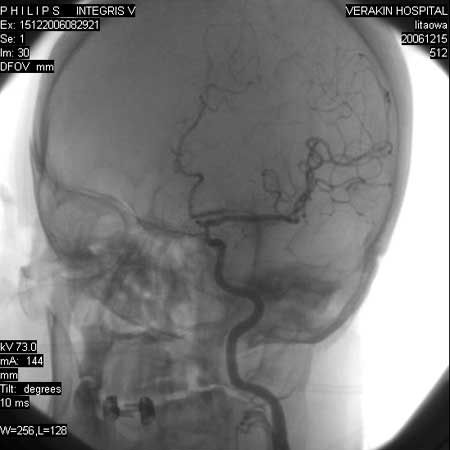

标题: DSA0063:颈内动脉血管造影

女,60岁,行全脑血管造影,图片较多,选了左颈内动脉造影100幅图中的10幅图片,请包涵。

做的是球管180度旋转摄影,共有100幅图只选了几幅图。

可以减影,机子是飞利浦的,性能应该不错。

头颈部旋转dsa技术是系统在开始曝光采集图像的同时,c形臂支架围绕患者做2次旋转运动,第1次旋转运动从注射对比剂后约2 s开始,获得一系列不同角度的含对比剂图像,称为对比像(contrast)。观察显示器,当病变血管的对比剂消失后,第2次旋转运动从对比像的结束位置开始,结束于对比像的起始位置,从而获得一系列减影所需的蒙片(mask),旋转dsa在采集实时图像时,以非减影方式显示,经过后处理,在回放时可分别得到相应角度的减影图像,清晰地显示血管解剖学的结构和形态。